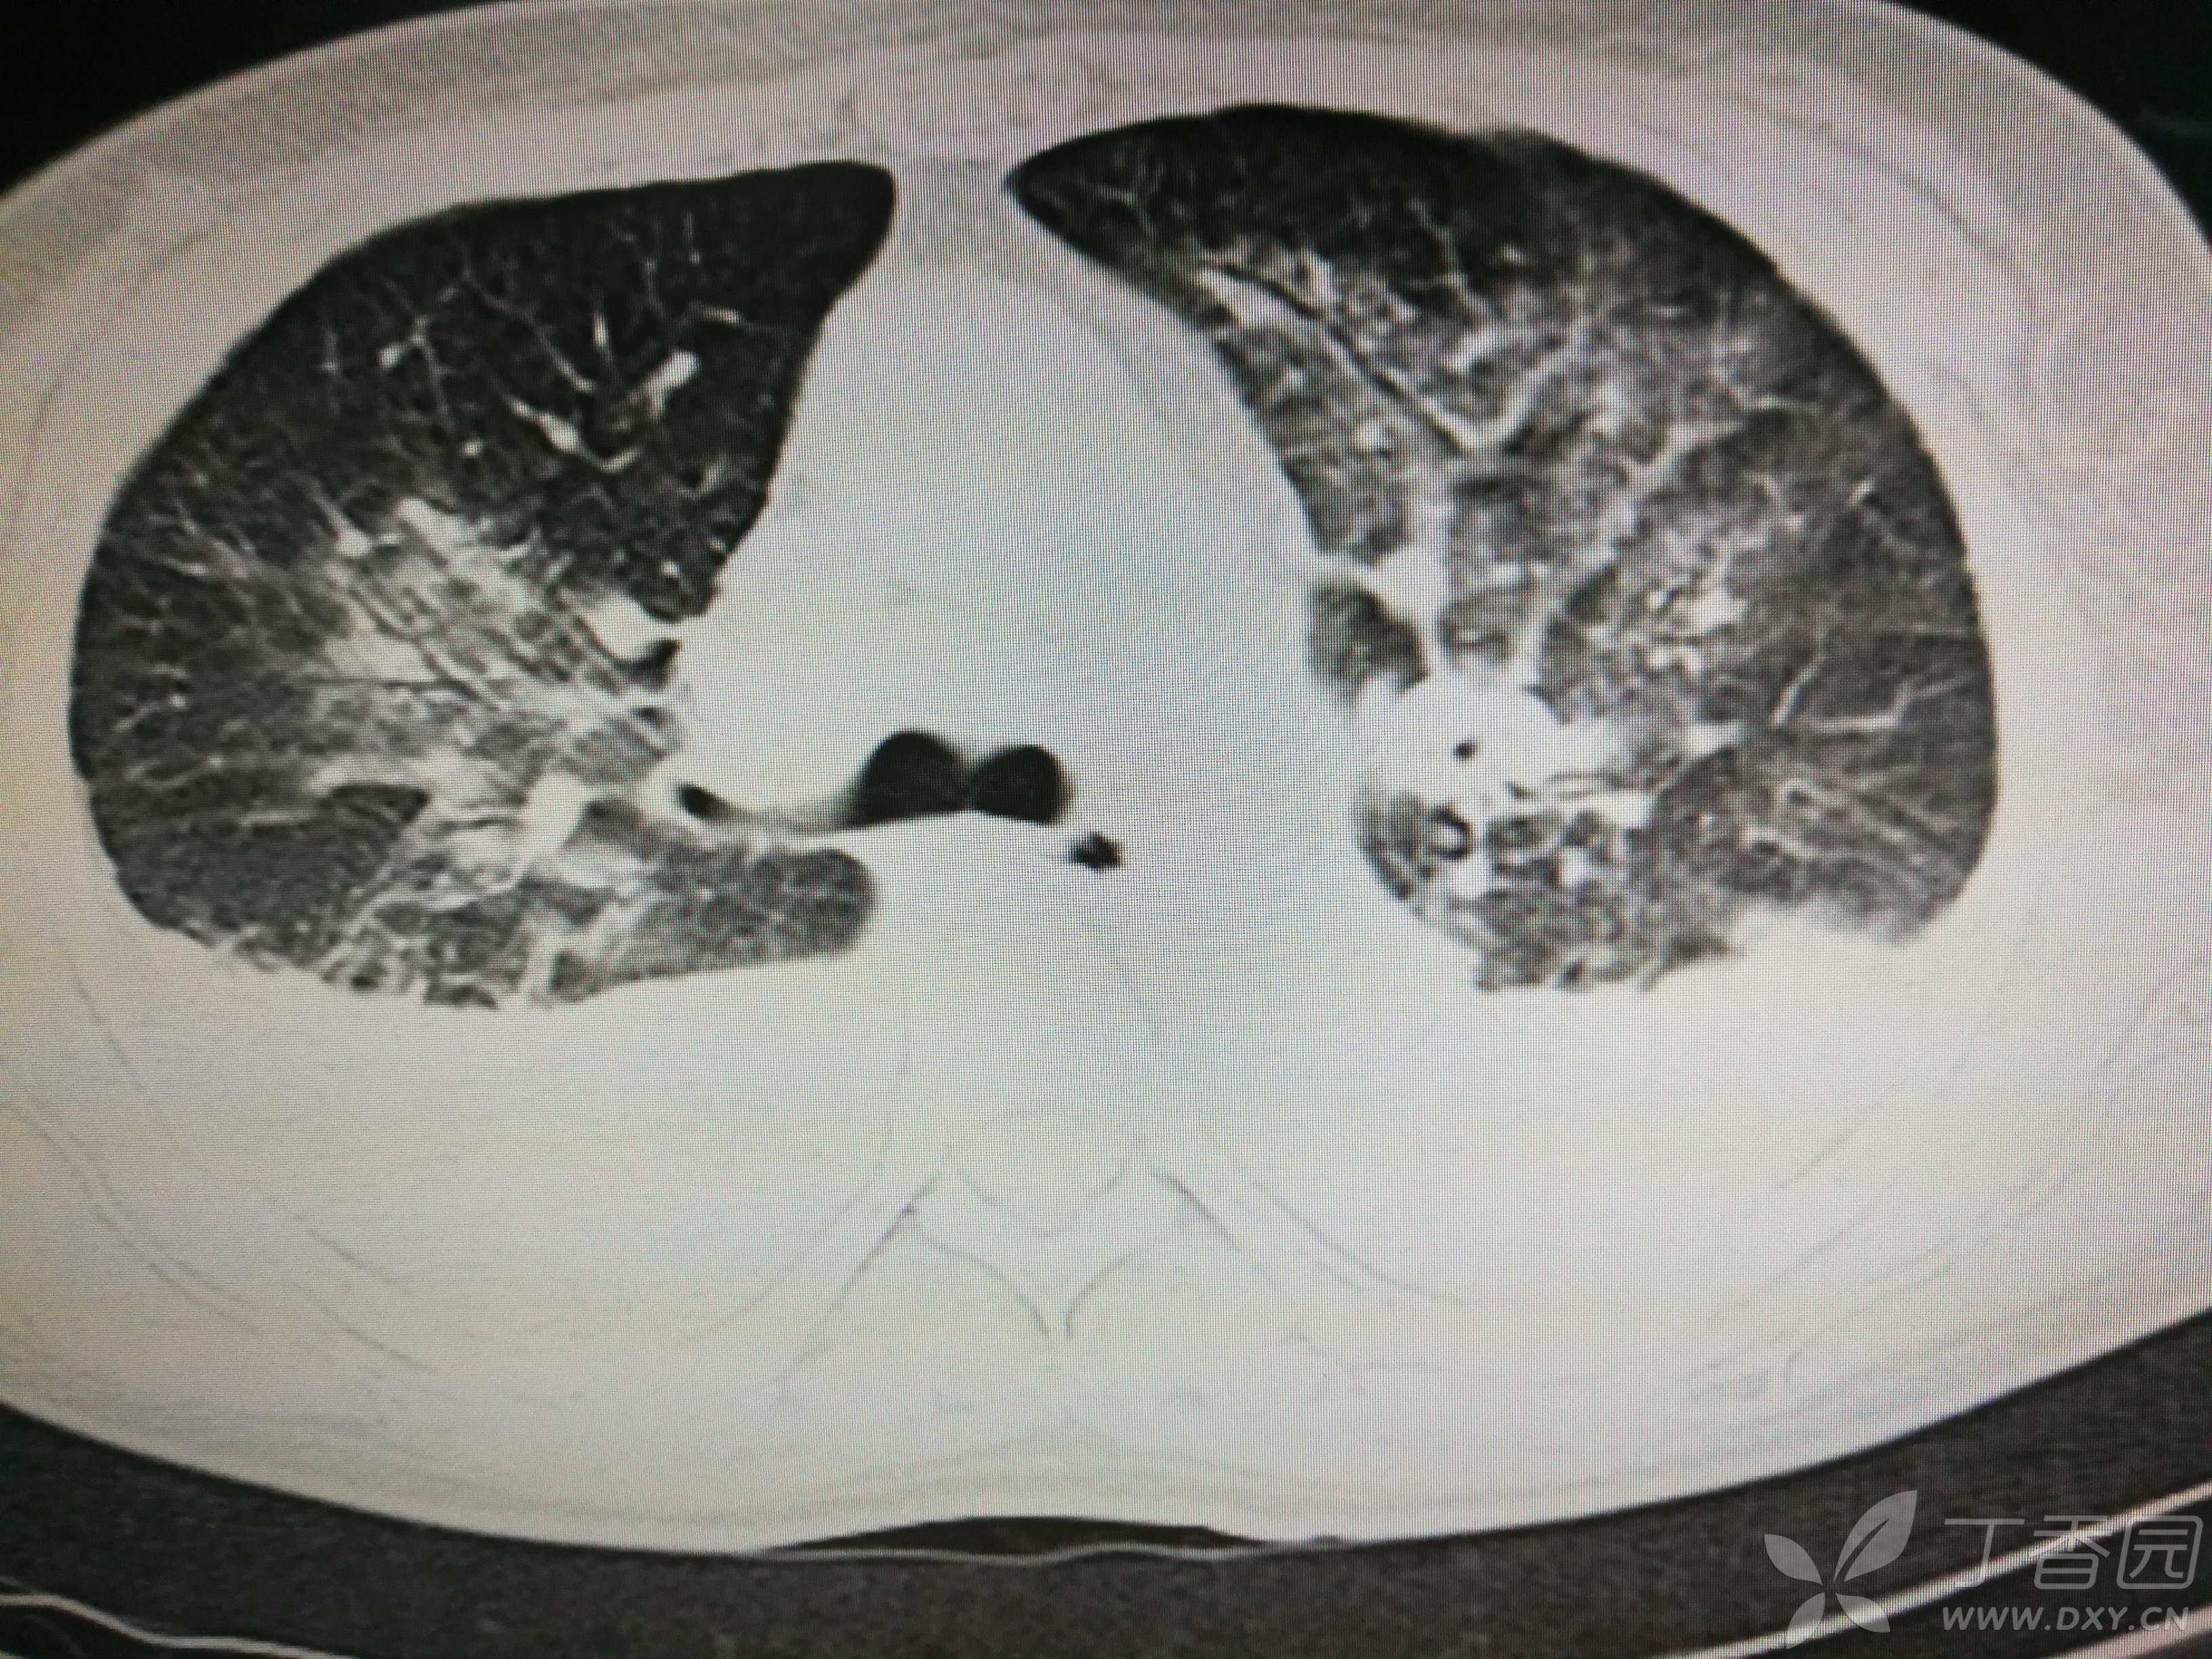

给予低分子肝素钙针抗凝、七叶皂苷钠针消肿及骨牵引固定等等治疗。入院后第四天行“左侧股骨下段骨折切开复位内固定术”(术前查双下肢彩超:双下肢深静脉血流通畅),手术顺利,术后予预防感染、预防血栓形成等治疗。术后患者无明显发热,生命体征平稳。术后第四天复查血常规:白细胞13.4×109/L,血红蛋白84g/L,血小板在正常范围。生化:白蛋白35.7g/L,余无明显异常。当天,患者开始出现轻度胸闷气急,可耐受。术后第五天患者胸闷气急加重,无胸痛,无背痛,无咯血,无意识障碍,无头晕头痛,无恶心呕吐等,急查凝血功能:纤维蛋白原降解产物12mg/L,D二聚体4000ug/L,余无明显异常。查动脉血气分析:pH7.52,氧分压62mmHg,二氧化碳分压30mmHg,碱剩余1.8mmol/L,乳酸1.0mm/L,血红蛋白86g/L。查胸部CT见下(先视频后图片):